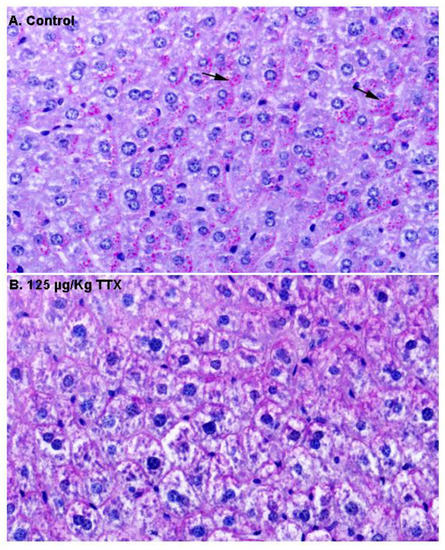

First, liver samples were stained with H&E (Figure 2). In contrast to liver sections from control mice, in which hepatocytes showed an eosinophilic cytoplasm and a round nucleus (Figure 2A), hepatocytes in the livers of mice fed daily with TTX at 125 µg/kg during 28 days showed a more vacuolated (non-stained) cytoplasm (Figure 2B) that could represent cellular swelling, lipid accumulation, or glycogen stores.

Next, in order to gain more insight into the content of these vacuoles, additional liver sections from control and TTX-treated mice were stained with PAS (Figure 3). As shown in Figure 3A, hepatocytes from control mice were strongly stained with PAS, and magenta granules (indicated by the arrows) considered to represent cytosolic glycogen were observed, while these granules were less evident in hepatocytes from TTX-treated mice (Figure 3B).

Figure 2. Representative hematoxylin–eosin (H&E) staining of the liver parenchyma in a sample from a control mouse (A), and from a mouse treated with 125 µg/kg oral TTX for 28 days (B). Compared to hepatocytes from control animals, more cytoplasmic vacuoles (non-stained spaces, indicated by arrows) were present in the hepatocytes from TTX-treated mice. In both cases, 600× microscope magnifications are shown.

Figure 3. Periodic acid–Schiff (PAS) stained liver sections from control mice and mice treated with TTX at 125 µg/kg (600× magnification). Hepatocytes from control animals were PAS positive, with glycogen (magenta granules indicated by the arrows) located in the cytoplasm (A), while these granules were not present in the hepatocytes from mice dosed daily with 125 µg/kg TTX (B).